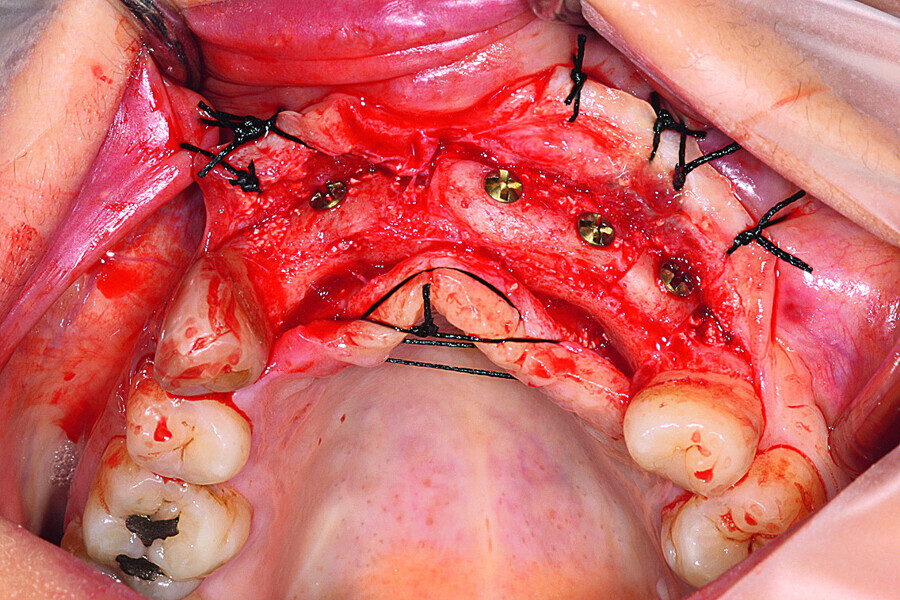

Fig. 6: The grafts were harvested from the chin symphysis and firmly attached by surgical screws in the recipient site.

Fig. 7: The grafts were harvested from the chin symphysis and firmly attached by surgical screws in the recipient site.